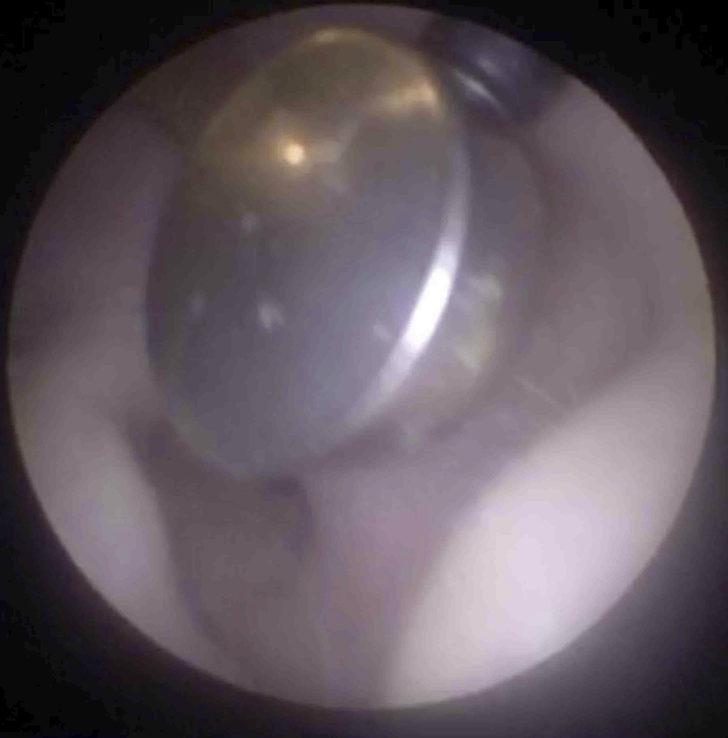

Mr. Neel Raithatha ise bu durum karşısında ilk olarak 4 mm'lik bir endoskopi aleti kullanmayı planlasa da kulak çapı için uygun olmayacağından bu kararından vazgeçerek bir mıktasından tardım alıyor.

İşitme cihazı pilinin bulunduğu noktayı bir kamera yardımıyla teşhis eden Mr. Neel Raithatha, ardından mıknatısı pile yaklaştırdı.

Kısa süreli bir uğraş sonucu pili kulak kanalından güvenle çıkarmayı başardı.